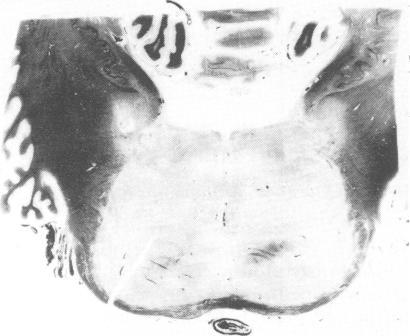

Ocular bobbing and myoclonus were unusual findings in a patient with central pontine myelinolysis. Pathological findings confirmed the diagnosis of pontine and extrapontine myelinolysis.

眼球摆动和肌阵挛在一位患有中央桥脑髓鞘溶解症的患者中是不常见的表现。病理检查结果证实了桥脑和脑桥外髓鞘溶解症的诊断。